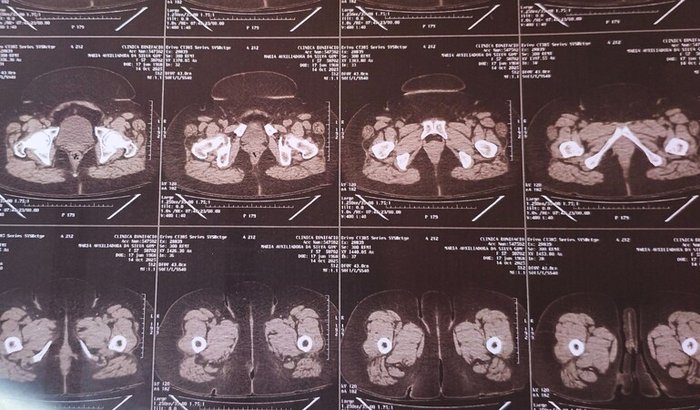

Olá, meu nome é Maria Auxiliadora, mais conhecida como Dora, e venho por meio dessa vakinha solicitar apoio, para fazer uma cirurgia de emergência, pois um cálculo renal se formou e já alcançou 12 mm. E agora desceu para a uretra e está comprometendo meu rim.